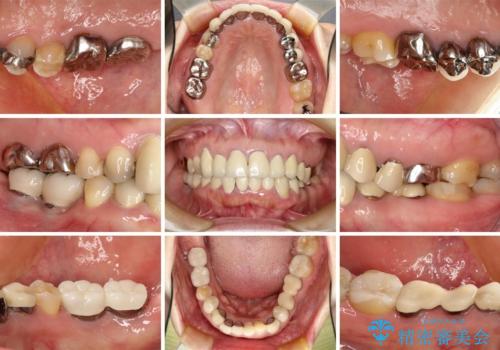

- 下顎の前歯に激痛を覚えて来院された患者様です。

取り急ぎ下顎前歯数歯の根管治療を、銀座しらゆり歯科医院長の林先生にお願いし、それ以外に気になっている、不自然な色調のクラウン、金属部分が見えてブラッシングがしにくいインプラント補綴、口元の突出感、出血のしやすい歯周ポケットなど、全てを解決するための治療を行うこととしました。